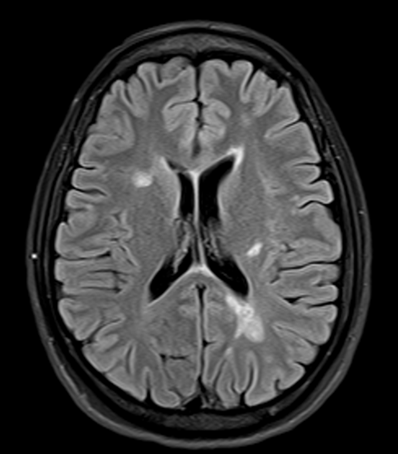

Description of Image 2

MRI scanning of patient 3 months after treatment

Significant reduction of brain lesion (brain damage)